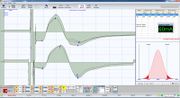

| 18:02, 15 February 2022 | Bilateral Electric Transcranial Stimulation.jpg (file) |  |

57 KB | Admin | == Details == {{CF | Descrizione = Motor Evoked Potential in hemilateral occlusal crossbite patient<br>''Motor Evoked Potential by electrical Transcranial Stimulation of the trigeminal roots. Note the structural symmetry calculated by the peak-to-peak amplitude on the right (upper trace) and left masseters (lower trace). (Nemus2, NGF; EBNeuro, Firenze, Italy)'' | Fonte = {{SF}} | Data = | Autore = Gianni Frisardi | Licenza = {{Cc-by-sa-4.0}} }} | 1 |